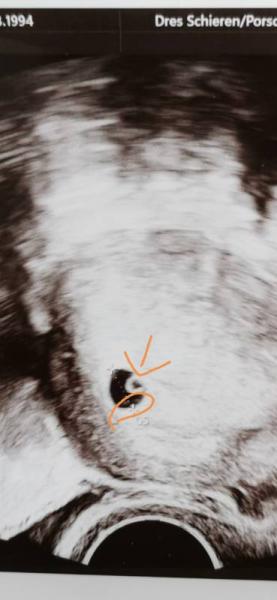

Hallo, Kann mir jemand erklären, was ich da sehe. Ich bin komplett neu. Einmal das am Pfeil, das ist der Dottersack? Sieht man auch schon mehr? Und im Kreis die weißen Flecken, was könnte das sein? Könnte man in so einem Stadium schon zwillinge erkennen? Ich bin Neuling... Bitte nicht steinigen

Huhu, also eigentlich müsste dir dein Frauenarzt das ja erklärt haben :D Sollte er zumindest tun. Vorallem wenn du zum ersten Mal schwanger bist. Das was du da siehst, ist deine Gebärmutter mit der Fruchthöhle. Also die kleine schwarze Blase. Darin siehst du einmal einen weißen Kreis, dass ist die Eizelle mit dem Dottersack. :)

Einen Zwilling hast du hier nicht. Für Zwillinge müssten zwei solche Fruchthöhlen da sein.

Genau das ist der Dottersack in der Fruchthöhle :) Konnte man das Herzchen schon schlagen sehen oder hören? :) Alles Gute für dich!!

Hallo, Jetzt hast du ja schon einige Rückmeldungen erhalten. Das was du eingekreist hast ist einfach nur die Markierung vom Gerät für die Messpunkte.

Danke, aber ich meinte die zwei weißen Punkte daneben. In der Fruchthöhle selber Nicht das Kreuz.